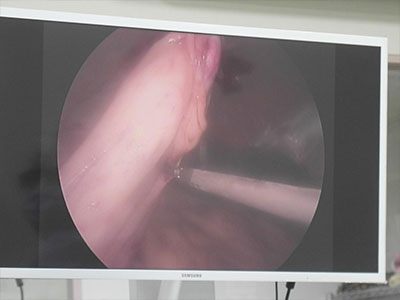

使用超音波刀燒灼血管和韌帶(出血量極少)